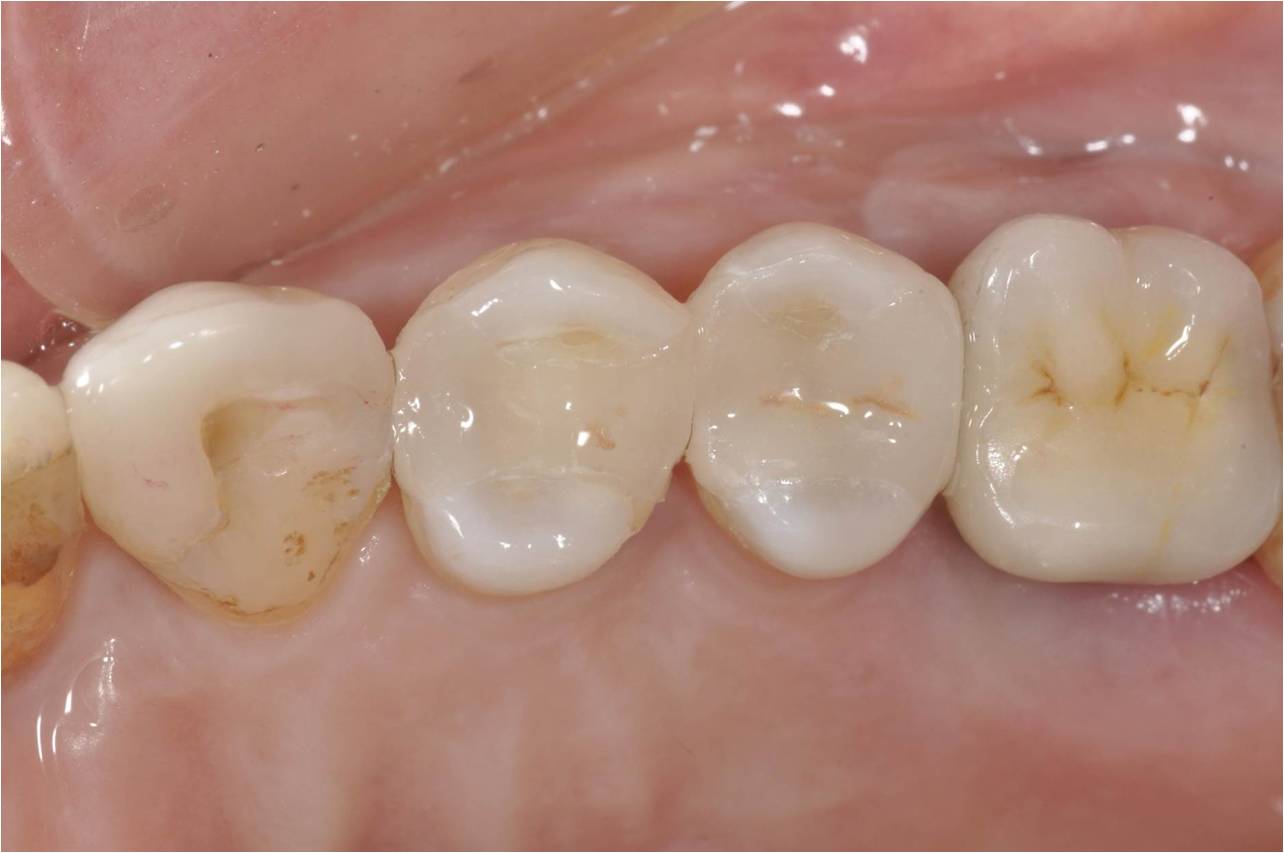

治療後

術前、術後比較